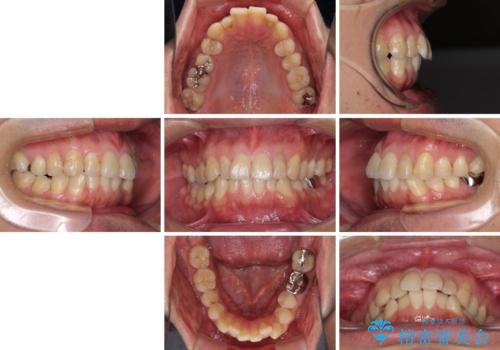

- 前歯のデコボコや八重歯を気にして来院された患者様です。

インビザラインを用いて、歯列を整えることとしました。